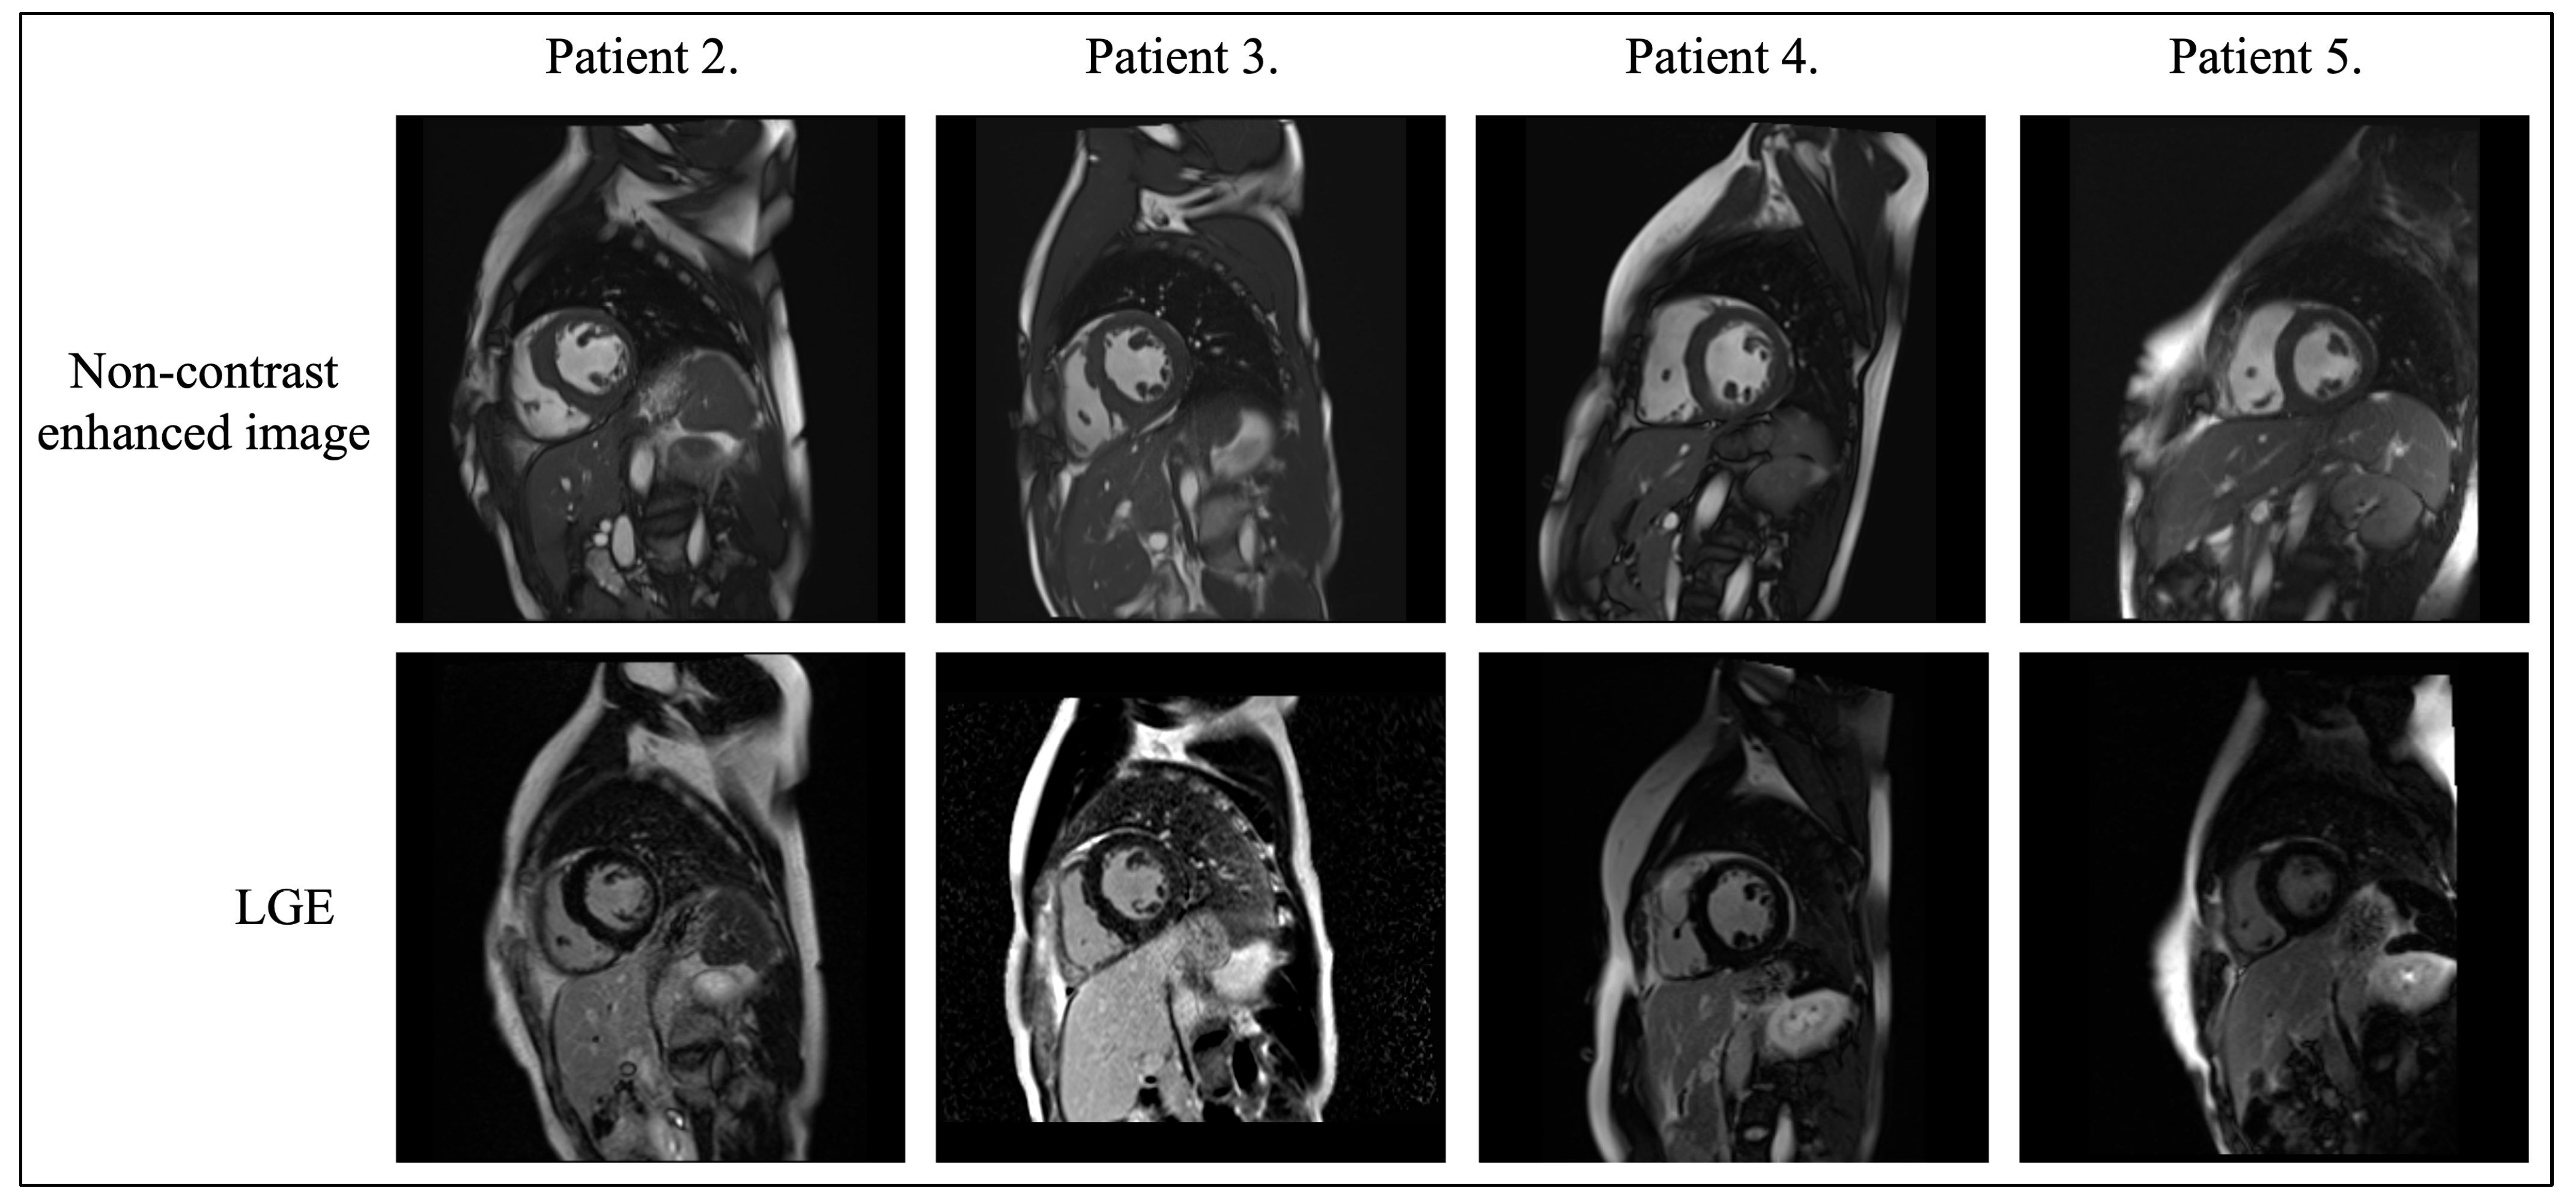

3.4. Cardiac Magnetic Resonance